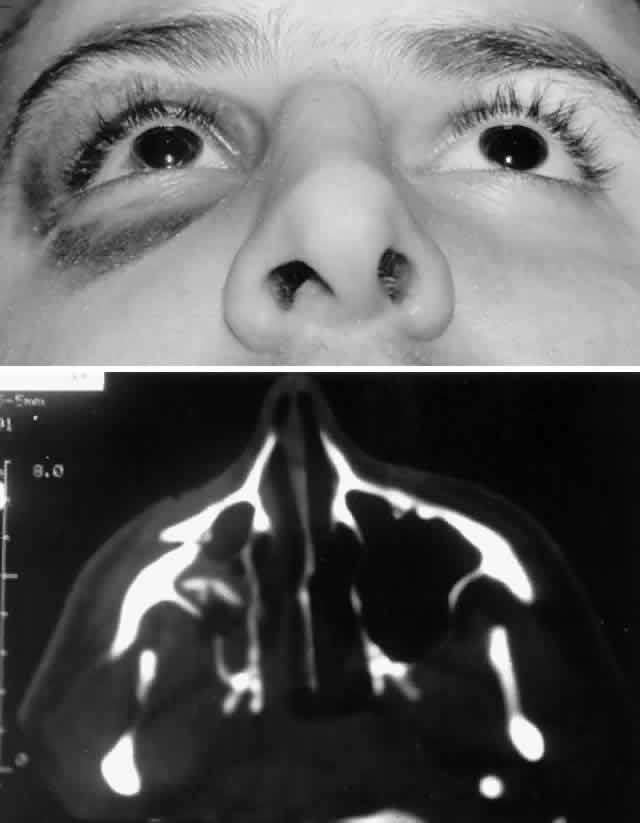

The position of the globe is also assessed (Fig. 3). As detailed previously, outward expansion of the orbital walls (blow-out fractures) can produce enophthalmos. Inward expansion of the orbital walls (blow-in fractures) can reduce orbital volume, potentially producing exophthalmos. In the early period after blunt orbital trauma, orbital edema and hemorrhage can transiently increase the orbital soft tissue volume, producing exophthalmos or “masking” the underlying potential for enophthalmos. As orbital edema subsides, the true globe position becomes evident. Over a more extended period of time (several months), soft tissue changes (cicatrization and, less commonly, fat atrophy) may contribute to the production of late enophthalmos. Globe position can be grossly assessed by direct visual inspection. Viewing the axial projection of the globes from above (“bird's-eye view”) or from below (“worm's-eye view”) facilitates a gross determination of axial globe position.

Fig. 3. A. Patient with blunt left orbital trauma demonstrates moderate enophthalmos of left eye (note deep superior sulcus). B. Slight restriction of supraduction in the left eye.

Quantitative exophthalmometry is performed for formal measurement of the degree of axial globe malposition. A difference of greater than 2 mm is considered abnormal. Typically a difference equal to or greater than 3 mm is required to produce an obvious clinical difference between the two eyes, although preexisting lid and facial morphology (e.g., prominent dermatochalasis or eyebrows) may make the difference clinically less obvious and minimize disfigurement. It is important to note that standard Hertel exophthalmometry may not be accurate if the lateral orbital rim is disrupted. The globe may also be displaced in a nonaxial direction, generally toward the area of least resistance. Hypo-ophthalmos (i.e., downward displacement of the globe) associated with disruption of the orbital floor is the most common nonaxial type of displacement. Globe dystopia can be assessed by the relationship of the globe to the surrounding anatomic landmarks and the contralateral eye (if not involved by the injury). Typically with hypo-ophthalmos, the globe sinks downward and the inferior corneal limbus may drop below the lower eyelid margin, producing a “setting sun” appearance. Globe dystopia can be measured with a ruler, noting the distance and direction of globe displacement in millimeters. In extreme cases of orbital floor disruption, the globe may actually subluxate into the maxillary sinus.33